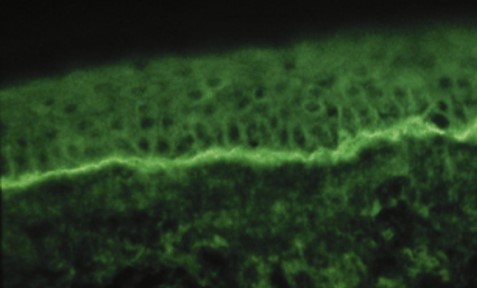

DIF: